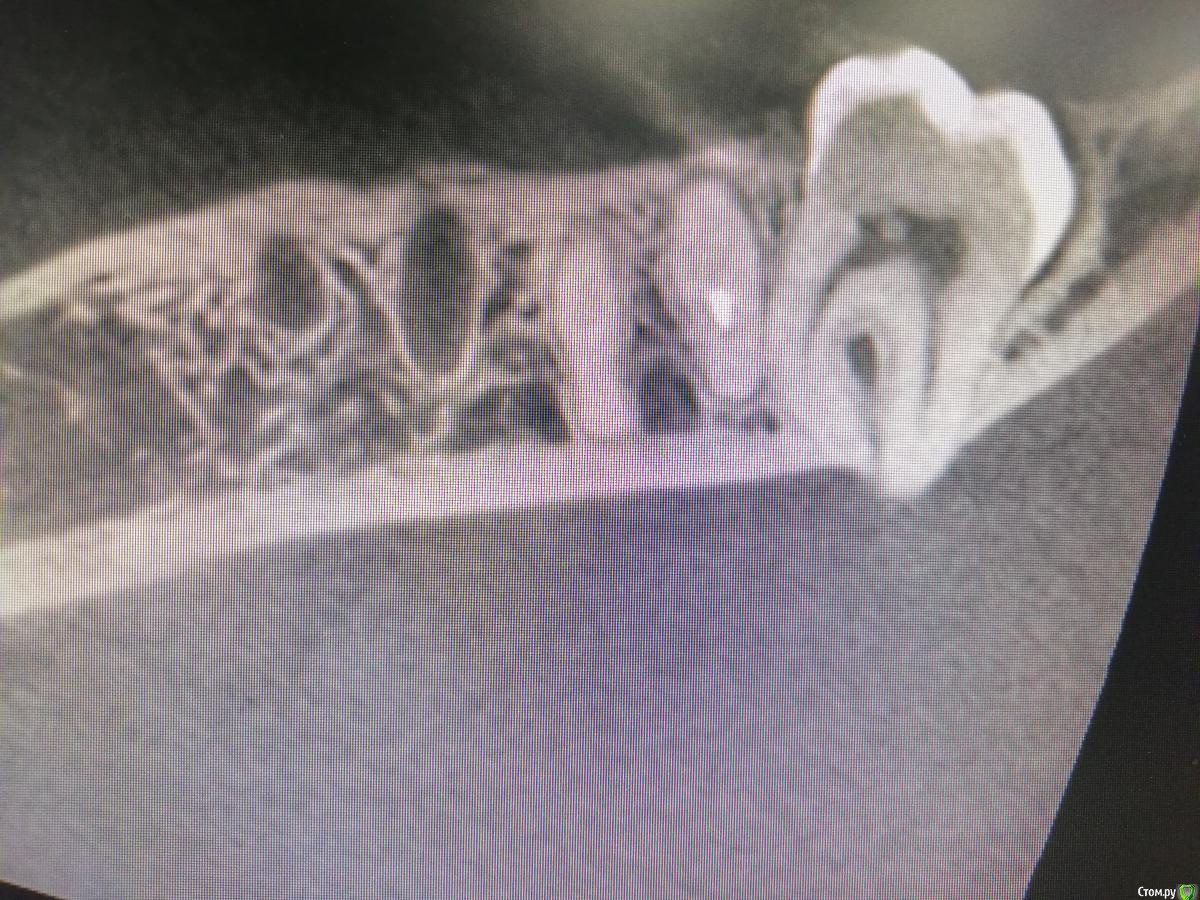

Женька Опубликовано 4 июня, 2020 Поделиться Опубликовано 4 июня, 2020 Коллеги, подскажите, что вы делаете когда вот так? Извините пожалуйста, за огромные фотки. Сегодня пациент придёт, позавчера было удаление. Вчера звонила жена (пациента), температура, отёк все дела. После удаления в лунку Белкозин + пара швов. Ссылка на комментарий

red_butler Опубликовано 4 июня, 2020 Поделиться Опубликовано 4 июня, 2020 Бугор ушёл? Ссылка на комментарий

Женька Опубликовано 5 июня, 2020 Поделиться Опубликовано 5 июня, 2020 Бугор ушёл?Именно, спросил у коллеги, посоветовал удалять элеватор, а не щипцами...Но здесь никаких щипцов...Люксатор+элеватор, боялся, что сломаю апексы, но решил покачать попробовать, в итоге качнулся очень хорошо, стал доставать и вместе с бугром. Вчера пациента осматривал, отёк, тем-па 36.1, дискомфорт и запах неприятный. Швы снял, губку частично достал (что прикрепилось не стал отрывать), промыл струйно, и резинку засунул с метрогилом Аб, нпвс назначил... Ссылка на комментарий